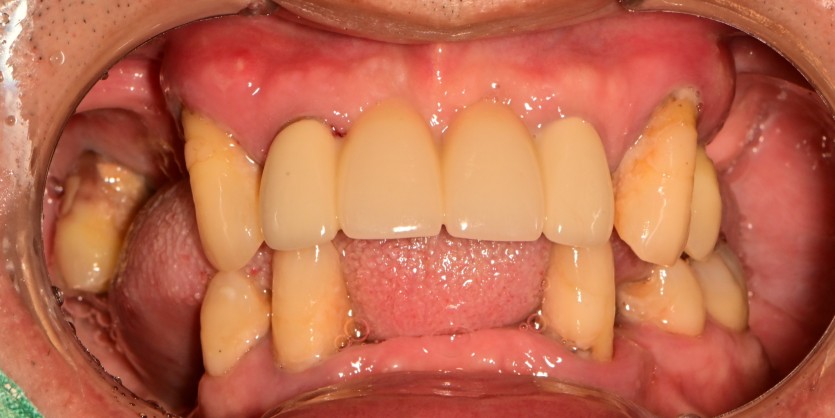

만 56세 전체 임플란트 증례

전체 임플란트 증례입니다.

18개의 임플란트로 완성하였습니다.